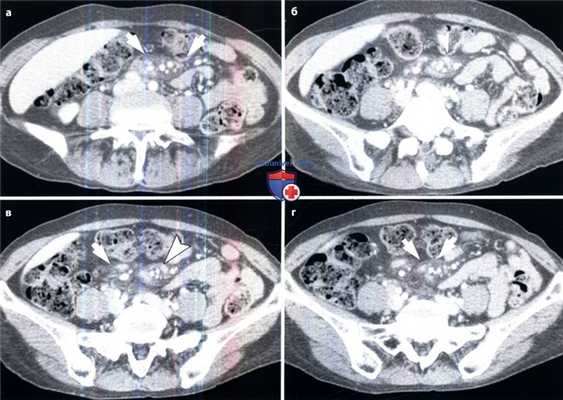

(а-г) На аксиальной КТ в венозную фазу контрастирования визуализируется помутнение ограниченного участка брыжейки (стрелки) с наличием мелких лимфатических узлов (указатели).